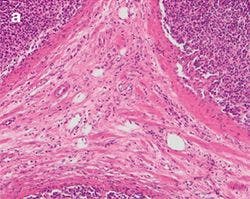

The practical effect of the color shift caused by a generic LED light source, both with and without a CC filter, is clearly visible when imaging a stained tissue section using the different light sources. Figure 5 shows a tissue section illuminated by the three different light sources mentioned before.

Figure 5: Stained Tissue Section a

Differences between halogen lamp (a) and LED illumination (b) lead to tissue stainings shifting to blue, both through the oculars and on the screen. Adding a CC filter (c) mitigates the issue, but still gives a yellowish appearance.